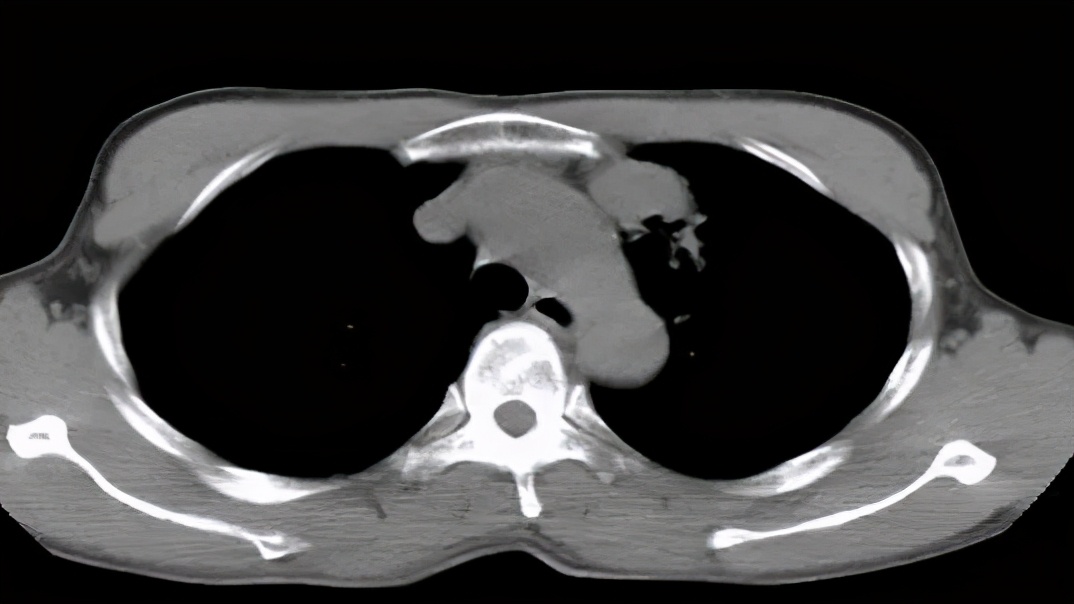

图:2017-1 胸部CT:左肺上叶后段团片影,较前片有所减小;两肺多发炎症,较前片部分吸收;右侧胸膜增厚、胸腔积液,较前片有所增多。

图:胸部CT:右侧液气胸,右肺实变,伴空洞及气液平。